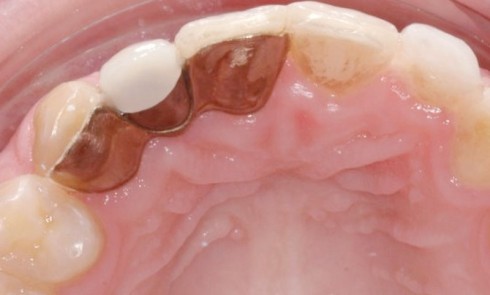

Article réservé à nos abonnés Agénésie d’incisives latérales maxillaires

Face à une agénésie d’incisive latérale la décision est difficile entre les diverses possibilités thérapeutiques envisageables. Chaque cas est unique...